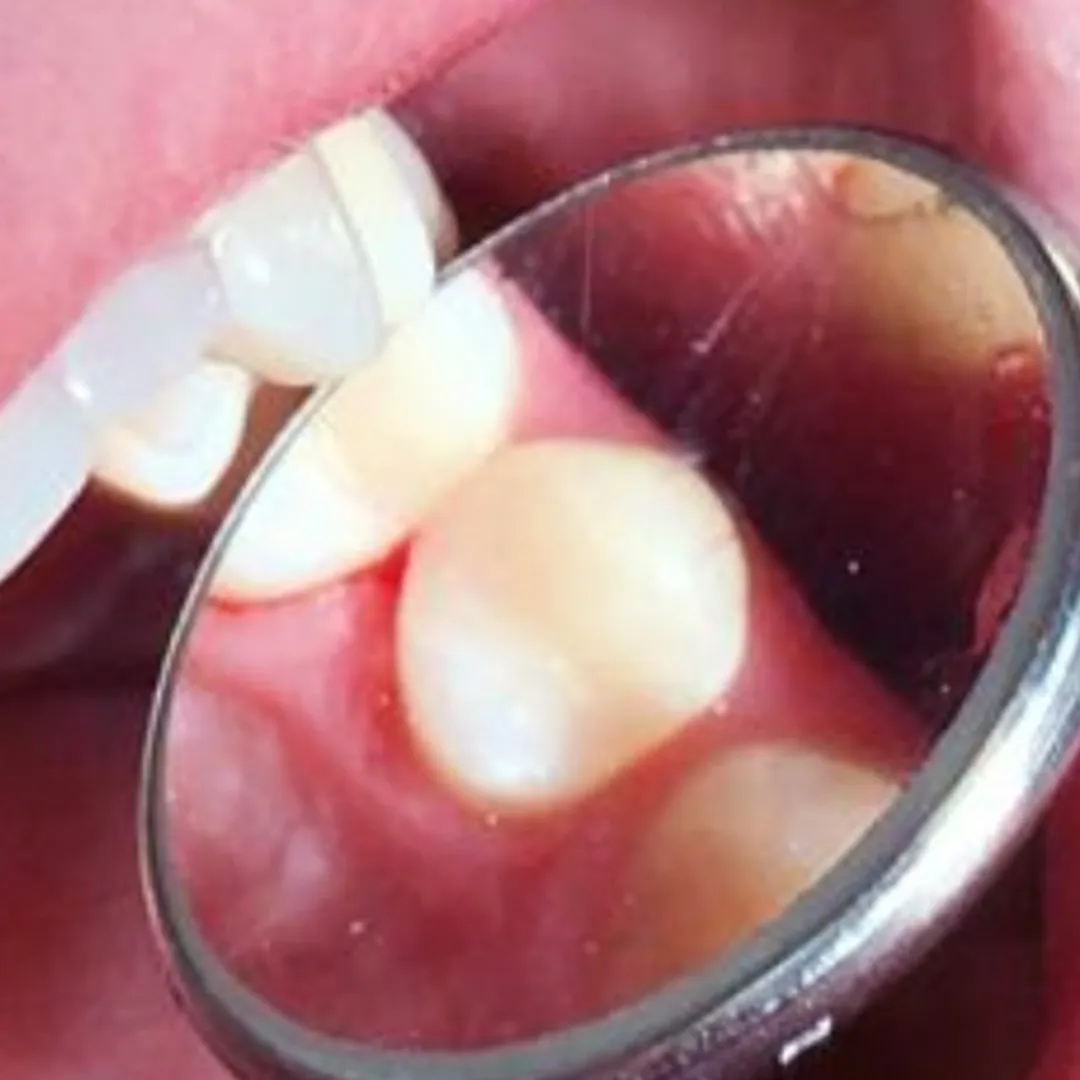

Пациент обратился в «Стоматологию Комфорта» с жалобой на острую боль в области нижних резцов, возникшую после начала лечения в другой клинике. В ходе осмотра и по результатам диагностики врач стоматолог-терапевт Вахлюева Елена Сергеевна поставила диагноз — периодонтит в стадии обострения.

В процессе лечения проведены следующие манипуляции:

- эндодонтическое лечение зубов 3.1, 3.2, 4.1, 4.2;

- пломбировка корневых каналов;

- временное восстановление коронковой части зубов.